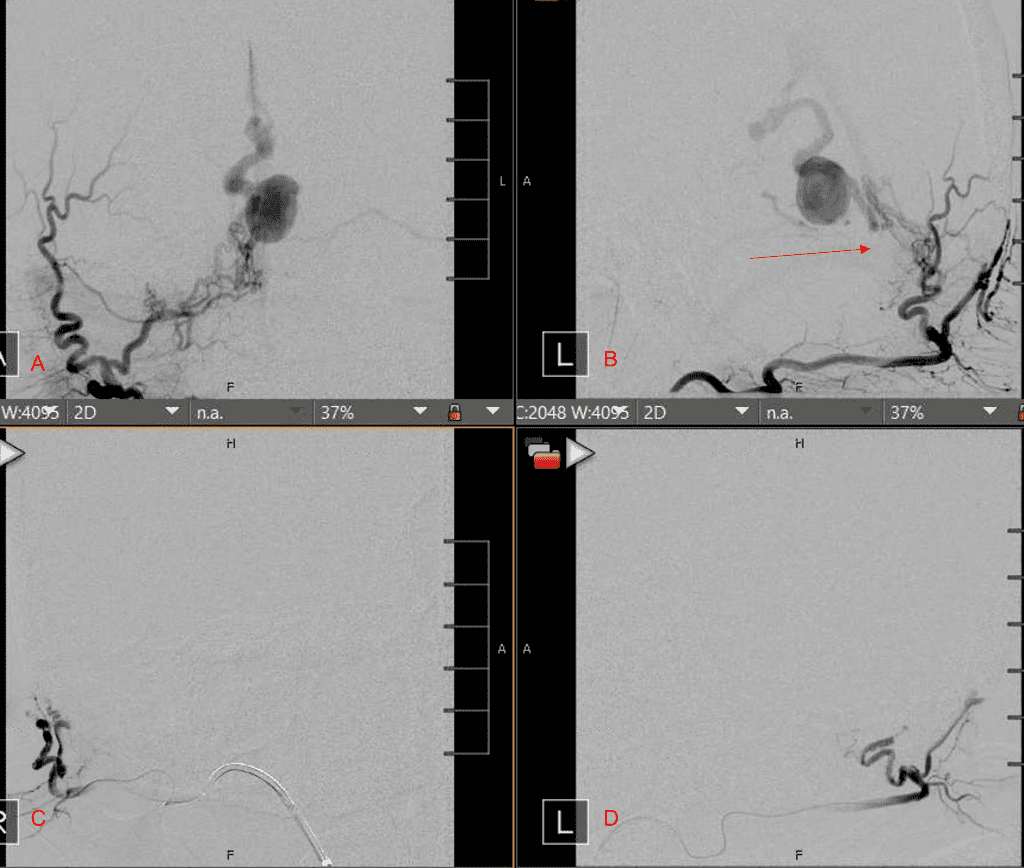

Figure 3. Right ECA AP and Lateral angiograms Pre (A and B) and Post NBCA embolization (C and D) Demonstrate near complete obliteration of right Occipital and Middle Meningeal Artery Fistulas